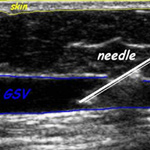

- With you lying down ultrasound scan will be used to locate the abnormal vein. The vein is punctured through the numbed skin to introduce a very thin tube (catheter) into the main trunk of the superficial venous system

- The skin is numbed, under ultrasound guidance, a catheter is inserted through a needle stick into the abnormal vein.

- Under ultrasound guidance the abnormal vein is punctured

- Ultrasound guided sclerotherapy

- The vein is punctured under direct guidance of the ultrasound view.